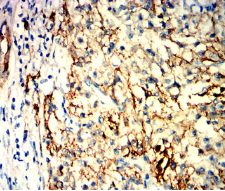

CDK4 Mouse Monoclonal antibody[4G9F1]

IHC    1/200 - 1/1000